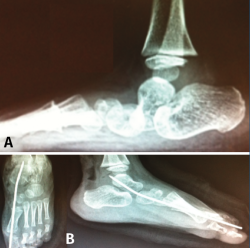

Astrágalo vertical congénito

El astrágalo vertical congénito es una deformidad rara que consiste en un pie plano rígido, dando aspecto de pie en mecedora. En casos severos, el astrágalo llega a estar alineado verticalmente con la tibia, pudiendo evolucionar a pie en piolet. Se caracteriza por valgo y equino del retropié, con dorsiflexión al nivel del mediopié y abducción del antepié causada por una luxación dorsal y lateral del navicular respecto a la cabeza del astrágalo, que se mantiene posicionado en flexión plantar rígida.

El manejo es casi siempre quirúrgico y se basa en una liberación periastragalina extensa, corrección del equino del retropié, liberación de las fuerzas pronadoras y trasplante del TA sobre la cabeza del astrágalo. Dobbs(19) describió un tratamiento miniinvasivo basado en yesos seriados “antiponseti” reduciendo progresivamente la articulación TN llevando el pie en equino y aducción. Finalmente, se procede a una fijación temporal de la alineación TN con AK y corrección del equino mediante tenotomía de Aquiles (Figura 17). En caso de reducción insuficiente, se añade una liberación TN para permitir la reducción completa, que se mantiene temporalmente mediante AK retrógrada.

Figura 17. Astrágalo vertical congénito. A: diagnóstico radiológico; B: técnica Dobbs percutánea.